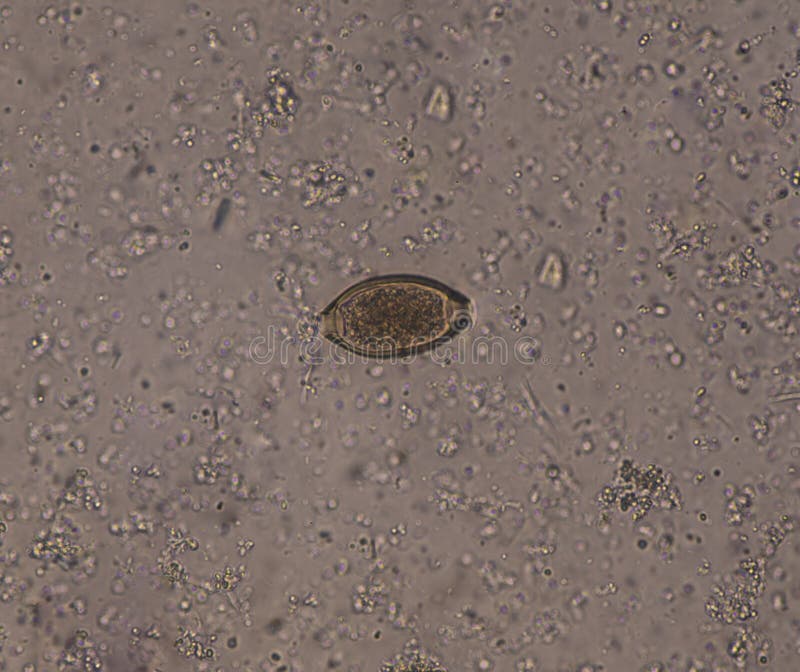

Stool microscopy revealing fertilized corticated eggs of Ascaris

Stool microscopy revealing fertilized corticated eggs of Ascaris Eggs Cause Loose Stools Learn if eggs are friend or foe for your ibs symptoms. Egg intolerance is a digestive condition that occurs when a person has difficulty digesting egg whites, egg yolks, or both. Cooking them makes them easier to digest. This intolerance may develop at any age, last several years, or cause a person to struggle their entire life. Yes, in most. Eggs Cause Loose Stools.